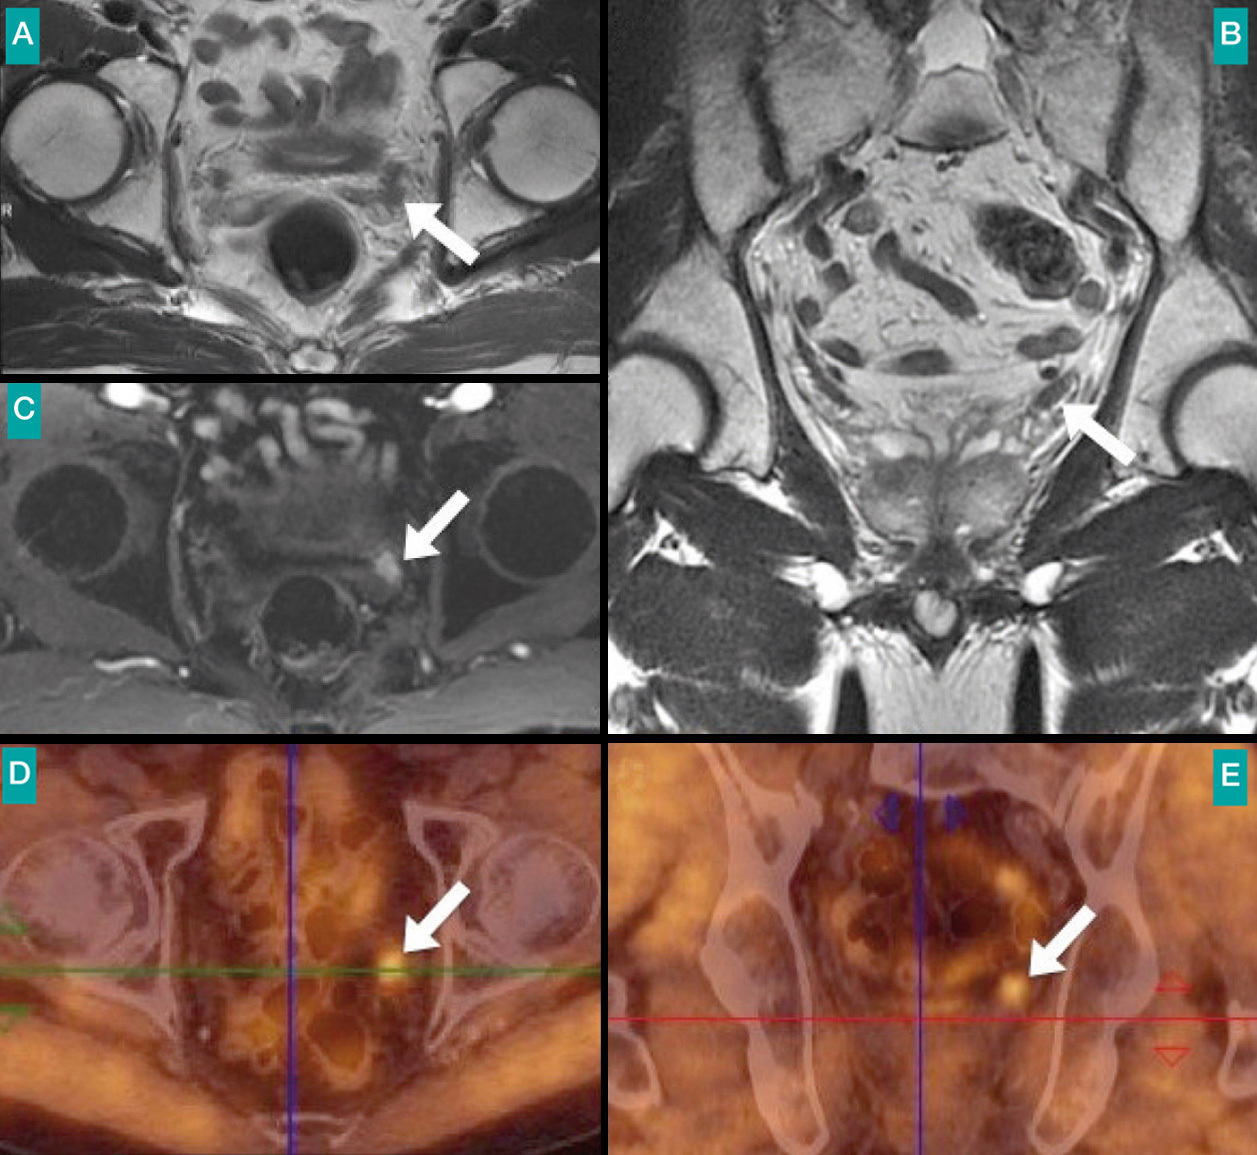

Patient de 71 ans traité 7 ans auparavant par radiothérapie pour un cancer de la prostate de score de Gleason 7. Rémission biologique puis réascension du PSA à 4,4 ng/mL. Rechute au niveau de la vésicule séminale gauche (flèche). L’imagerie par résonance magnétique (IRM) de la prostate en T2 (A, B) ne montre qu’un discret épaississement de la vésicule séminale gauche. L’IRM dynamique avec injection (C) montre une prise de contraste suspecte de la vésicule séminale gauche. La tomographie par émission de positons à la fluorocholine (D, E) confirme la rechute localisée à la vésicule séminale.